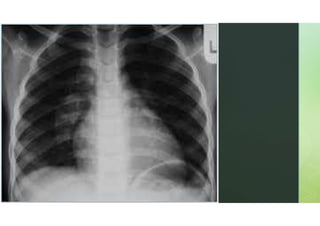

O QUE É?

 A tecnologia de Raio X funciona emitindo radiação que

atravessa o corpo e é captada por um detector ou

filme fotográfico.

 Os diferentes tecidos do corpo absorvem a radiação em

diferentes graus, criando uma imagem contrastante que

destaca ossos, órgãos e outras estruturas internas.

Tecidos densos, como ossos, aparecem brancos,

enquanto tecidos mais suaves, como músculos e

gordura, aparecem em tons de cinza.

DESVANTAGENS?

 A exposição à radiação, embora geralmente baixa,

pode acumular-se com exames repetidos,

aumentando o risco de efeitos adversos a longo prazo.

A radiografia também pode ser menos eficaz em

visualizar tecidos moles e em fornecer detalhes

comparáveis a outros métodos de imagem, como a

ressonância magnética (RM) ou a tomografia

computadorizada (TC).